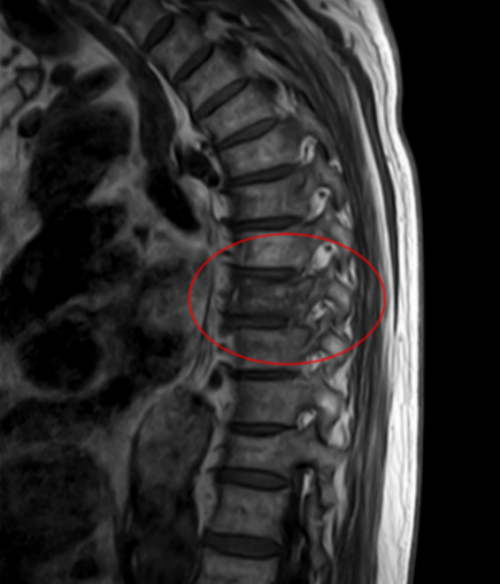

核磁共振显示王大爷T8胸椎压缩性骨折

据家属回忆,早在几年前,社区医生就提醒过老人,体检结果显示他有骨质疏松,需要重视。但老人自认为身体很健康,没太重视,直到这次因为举杠铃导致T8胸椎压缩性骨折入院,老人才认识到骨质疏松的危害。

香港马会app 脊柱外科二区主任曾浩介绍,王武成老人骨折的原因,并非简单的动作失误造成的,其根本在于老年性骨质疏松。骨骼如同建筑的钢筋,随着年龄增长,尤其是老年人,骨量自然流失,骨骼退化,导致骨密度下降、骨骼脆性增加。此时,骨骼承受外力的能力显著降低。像打沙袋瞬间的冲击力、举杠铃时脊柱承受的垂直压力,对于已骨质疏松的脊柱来说,可能已超出了安全负荷,从而引发骨折。尽管老人一直坚持健身,看上去身体很“硬朗”,但其骨骼的内部结构,已悄然进入了需要特别呵护的“脆弱期”。此外,还有一个不容忽视的原因:王大爷体重高达160斤,大基数使得骨骼同样长期受压,加剧了脊柱负担,更易致骨折。